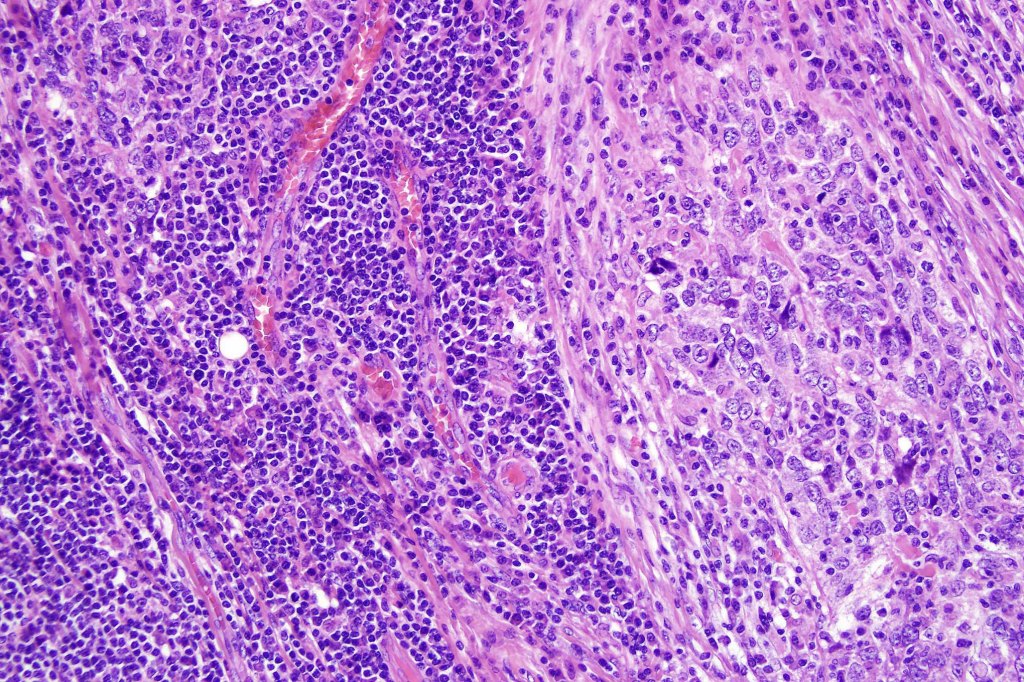

•Dermal generally circumscribed tumor nodule (less often it may show an infiltrative border)

•Syncytial epithelial component in nests, cords or sheets surrounded by an intense lymphoplasmacytic infiltrate

•Epithelial cells are large with abundant cytoplasm and vesicular nuclei with conspicuous nucleoli

•Marked mitotic activity, variable pleomorphism